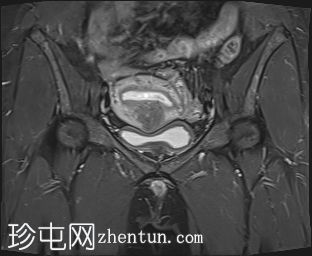

冠状位

STIR序列

4.jpg

增大的子宫腹股沟区(AVF)显示:

子宫前壁交界区局灶性增厚,边界不清。形成直径约3厘米的局灶性肿块样病变,轻度压迫膀胱。肿块边界模糊不清,可见多个细小出血灶,在T1加权像和T2加权像上均呈高信号,提示局灶性子宫腺肌症。

左侧卵巢可见数个小囊肿,在T1加权像上呈高信号,在T2加权像上呈低信号(T2阴影),T1脂肪抑制序列未见信号下降,提示其为血液降解产物。最大的囊肿轴位大小约为3.1×1.7 cm,轻度压迫卵巢实质。

边界模糊不清是局灶性子宫腺肌症(无包膜)的特征。此外,病灶内存在多个微小的内部出血灶(异位腺体),且邻近增厚模糊的交界区,这些都是局灶性子宫腺肌症的诊断标准。

少数左侧卵巢囊肿伴有上述出血信号,可能代表子宫内膜异位囊肿,因为多发性和双侧性更倾向于子宫内膜异位囊肿而非出血性囊肿。